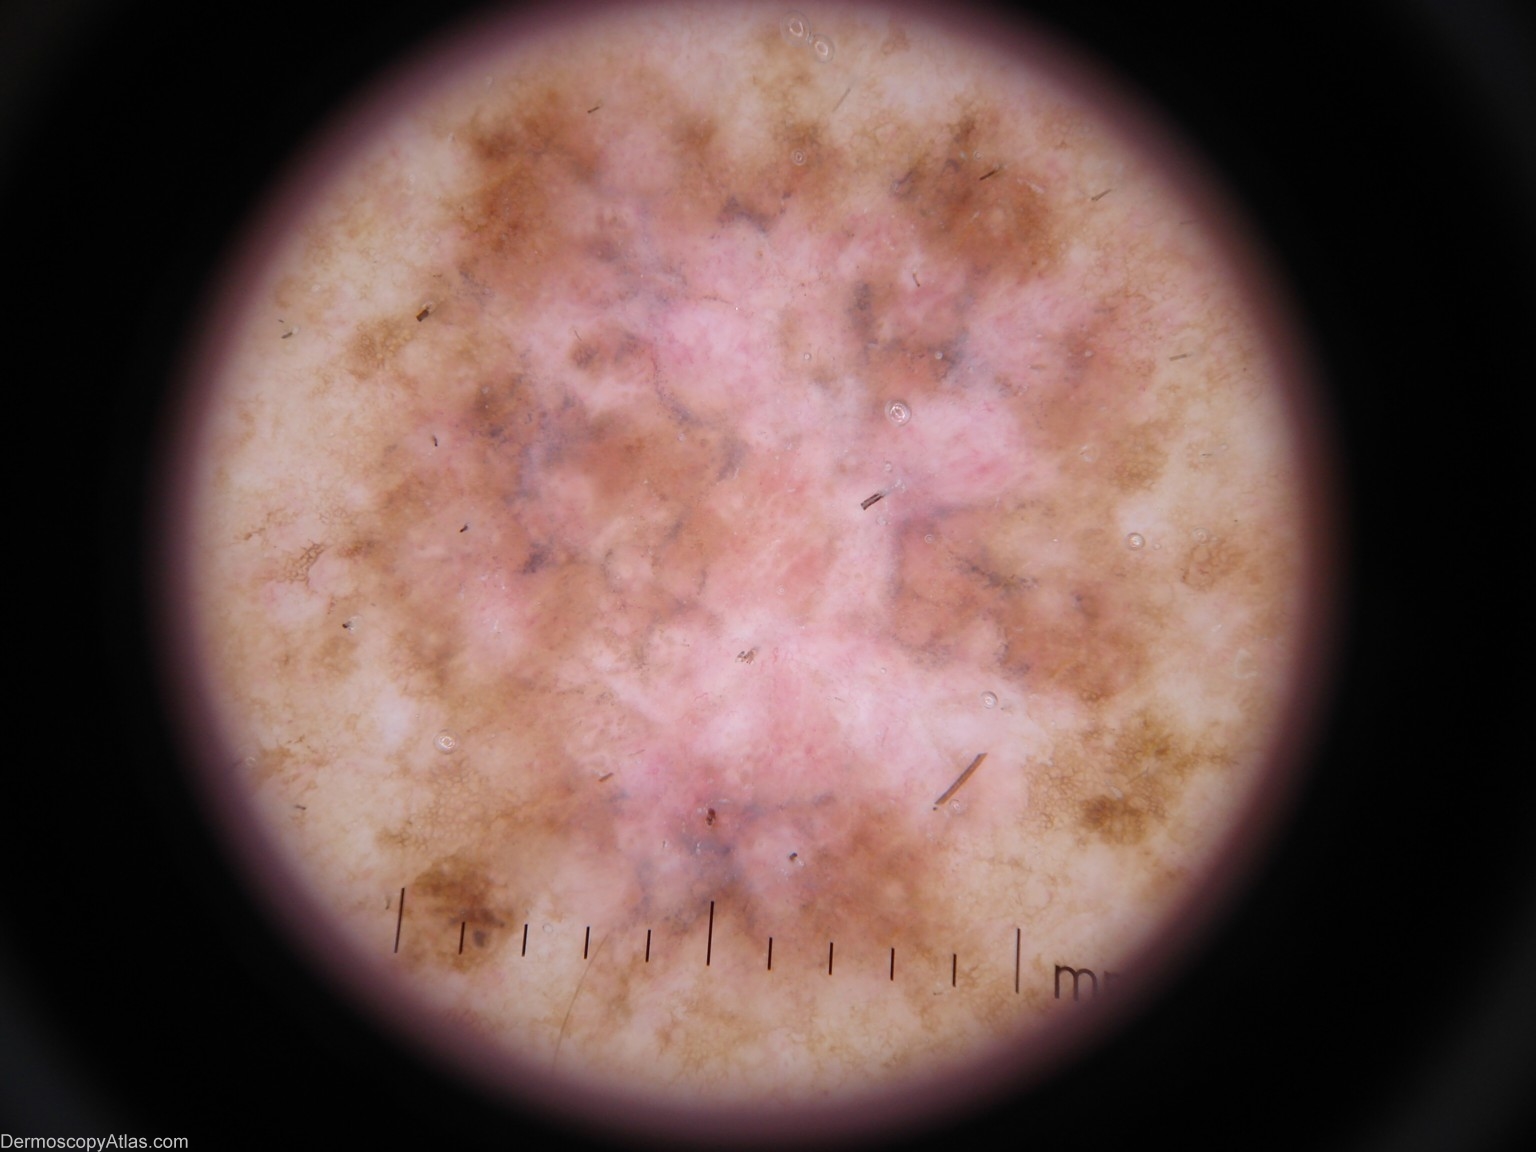

Diagnosis - Melanoma invasive

Diagnosis: Melanoma invasive